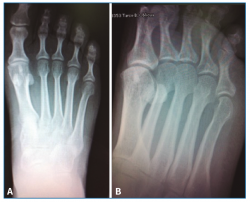

El estudio radiográfico en carga no mostraba alteraciones en la fórmula metatarsal ni lesiones óseas (Figura 1).

Figura 1. Radiología simple anteroposterior en carga (A) y oblicua antepié (B) sin lesiones óseas a nivel del 4.º metatarsiano.